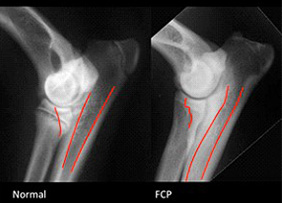

La Displasia del gomito:

La displasia del gomito (ED - Elbow Dysplasia) è una malattia scheletrica che colpisce l'articolazione del gomito e indica uno sviluppo anomalo dell'articolazione del gomito che porta ai fenomeni artritici, artrosici e al distacco di frammenti ossei. Con il termine "displasia del gomito" (ED) s’intende un insieme di patologie a carico dell'articolazione omero-radio-ulnare.

Le condizioni patologiche sono: FCP - Frammentazione del processo coronoideo mediale dell'ulna OCD - Osteocondrite dissecante del comparto mediale del condilo omerale UAP - Mancata unione del processo anconeo dell'ulna INC - Incongruenza dell'articolazione omero-radio-ulnare UME - Mancata fusione del condilo mediale dell'omero IOHC - Ossificazione incompleta del condilo omerale Una crescita asincrona di radio e ulna determina un’incongruenza articolare provocando dei traumi e delle alterazioni sui processi di ossificazione encondrale a livello di cartilagini di accrescimento e articolari. I sintomi di un soggetto colpito dalla displasia del gomito sono vari, si va da una zoppia dell'arto interessato più o meno accentuata con un movimento del gomito aperto verso l'esterno, e nei casi più gravi ad una immobilità dell'arto interessato. Nel 1989 si è costituito l'IEWG (International Elbow Working Group) che si è assunto il compito di identificare, definire e classificare gli aspetti patogenetici e le manifestazioni cliniche della displasia del gomito. Classificazione FCI della displasia del gomito: Salute Rhodesian 8 La displasia del gomito si presenta solitamente in forma bilaterale e si può rilevare una o due o più condizioni insieme. Le razze più colpite e le loro lesioni specifiche sono: Rottweiler, Bovaro del Bernese, Golden Retriever, Pastore Tedesco e Labrador Retriever, tuttavia numerose altre razze sono interessate da questa patologia e anche il Rhodesian Ridgeback, seppur in minor percentuale può essere interessato dalla displasia del gomito.